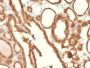

Epitope of this MAb is mapped between aa 202-212 of EGP40, which is a 40-43 kDa transmembrane epithelial glycoprotein, also identified as epithelial specific antigen (ESA), or epithelial cellular adhesion molecule (Ep-CAM). It is expressed on baso-lateral cell surface in most simple epithelia and a vast majority of carcinomas. Antibody to Ep-CAM has been used to distinguish adenocarcinoma from pleural mesothelioma and hepatocellular carcinoma. This antibody is also useful in distinguishing serous carcinomas of the ovary from mesothelioma.

IHC, FFPE (verified), WB (verified)

IHC (FFPE) (verified)|WB (verified)

Higher concentration may be required for direct detection using primary antibody conjugates than for indirect detection with secondary antibody|Immunohistology (formalin): 0.5-1 ug/mL for 30 minutes at RT|Staining of formalin-fixed tissues requires boiling tissue sections in 10 mM citrate buffer, pH 6.0, for 10-20 minutes followed by cooling at RT for 20 minutes|Optimal dilution for a specific application should be determined by user